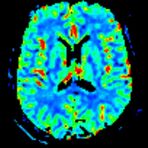

Spezialtechniken der Magnetresonanz

• Diffusionswichtung

• Perfusionswichtung

• Suszeptibilitätswichtung

• MR-Spektroskopie

Diese Verfahren werden bei verschiedenen Fragestellungen in verschiedenen Körperregionen in die Messprotokolle sinnvoll eingefügt. Teilweise können dadurch Differenzierungenverschiedener krankhafter Prozesse verbessert werden.